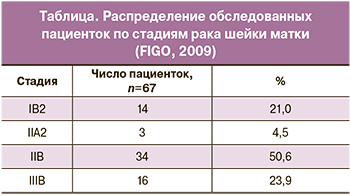

Морфологические варианты новообразований представлены плоскоклеточным раком – ороговевающим (52,0%) и неороговевающим (48,0%). Распределение пациенток по стадиям заболевания представлено в таблице.

Морфологические варианты новообразований представлены плоскоклеточным раком – ороговевающим (52,0%) и неороговевающим (48,0%). Распределение пациенток по стадиям заболевания представлено в таблице.